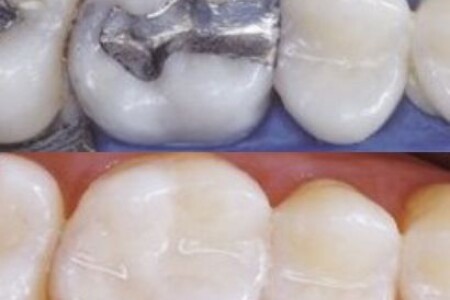

Da li su bolje bele ili amalgamske plombe?

Ovo je često pitanje pacijenata kada dođu kod zubara. Evo o čemu se tu radi. Amalgamske plombe se koriste dugi niz godina...